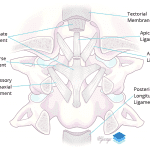

- Remember that the alar ligaments attach to the occipital condyle. Displaced avulsion fractures are considered unstable injuries concerning for underlying ligament injury, and while you do not need to know the surgical classification schemes, make sure to mention whether or not these fractures are displaced